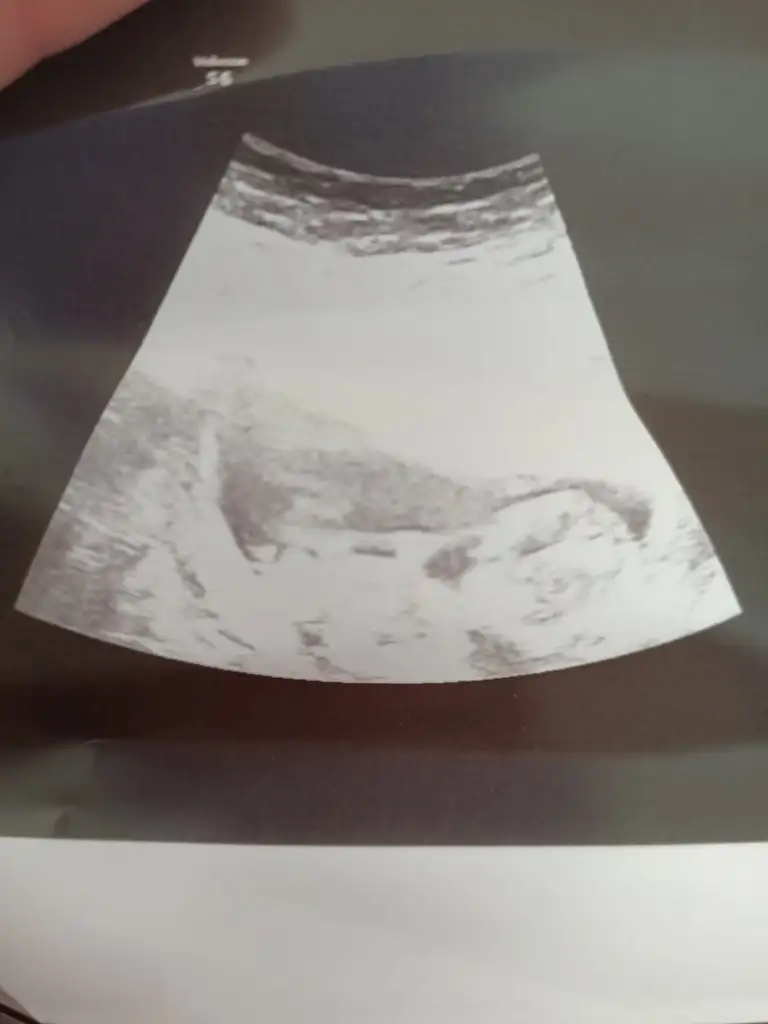

Ikra meyra merhabalar sanırım nub belli değil ama şansımı denemek istedim 11+2 yiz bugün tahmininiz nedir

Eklentiler

• IMG_20210428_103252.webp

14,5 KB · Görüntüleme: 53

çok merak ediyorum cinsiyetiiii